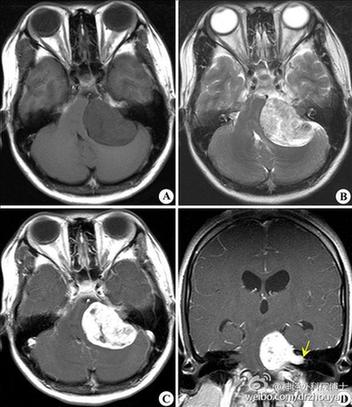

【5. 橋小腦角腫瘤】:除眩暈外,常伴有耳鳴及同側(cè)聽(tīng)力障礙,腫瘤較大時(shí)還可出現(xiàn)三叉神經(jīng)、面神經(jīng)、后組顱神經(jīng)損害表現(xiàn),腫瘤壓迫腦干和小腦,還可出現(xiàn)錐體束征、共濟(jì)失調(diào)和梗阻性腦積水。CT、MRI可明確診斷。